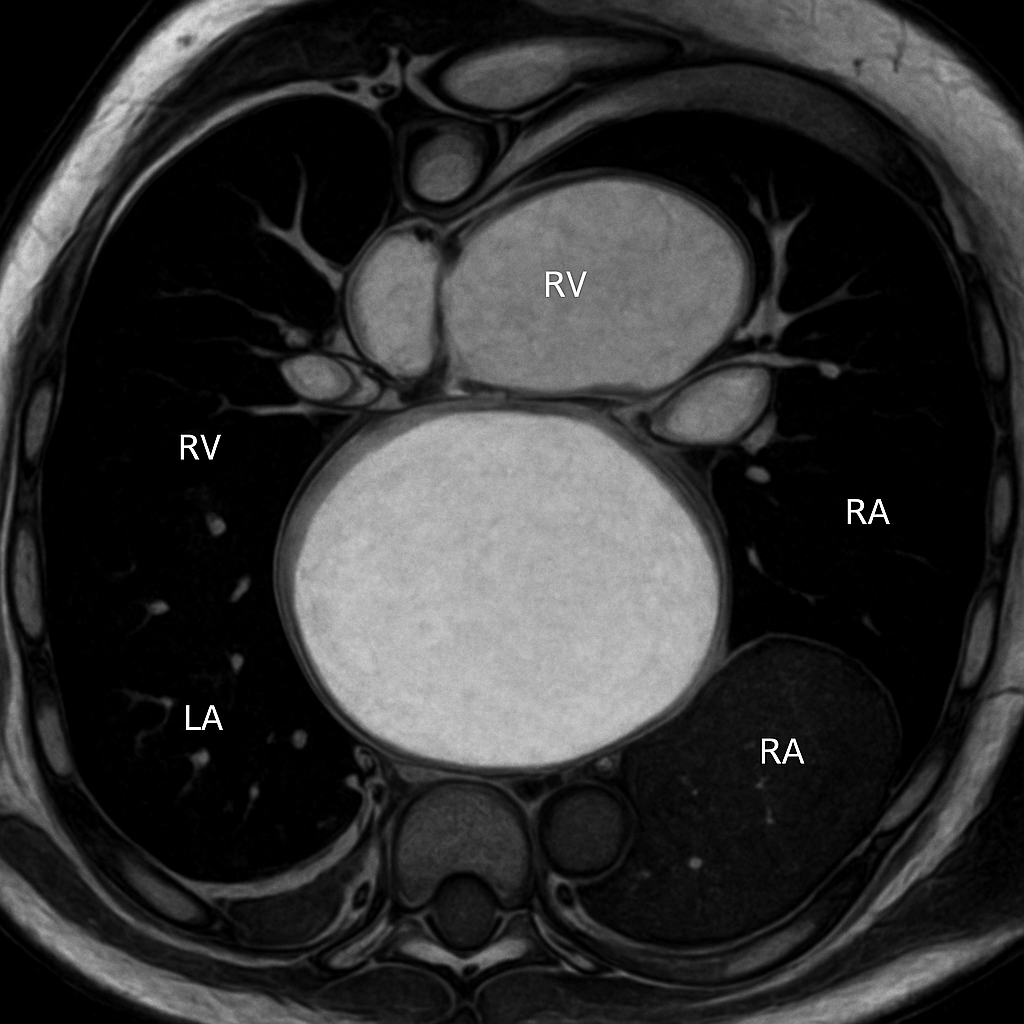

MRI — Short Axis Cine (Diastole)

Cardiac MRI short-axis (SA) view at mid-ventricular level during end-diastole. Balanced SSFP sequence showing bright blood in LV and RV cavities, dark myocardium, papillary muscles.

MRI AI Generated 2026-03-16

Ssfp Short Axis

bSSFP cine, mid-ventricular short axis, end-diastolic frame. Bright blood pool, dark myocardium.

OpenAI gpt-image-1

MRI — Short Axis Cine (Systole)

Cardiac MRI short-axis (SA) view at mid-ventricular level during end-systole. SSFP sequence showing thickened myocardium and small LV cavity.

Ssfp Short Axis Systole

bSSFP cine, mid-ventricular short axis, end-systolic frame. Show concentric LV wall thickening.